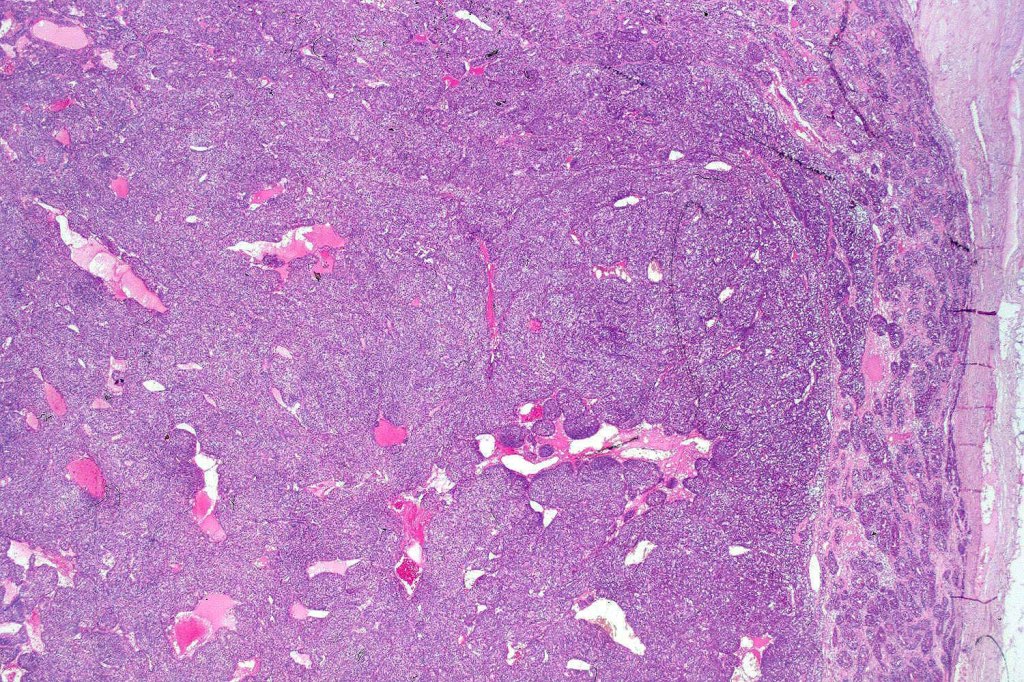

Histological features

•Pre-existent spiradenoma

•Malignant component shows loss of dual cell population, increased mitotic activity, atypical mitoses & necrosis

•The alternative classification into low grade (with only mild atypia and increased mitotic activity) and high grade variants has some merit although in any individual case this can be hard to apply unless the whole tumor has been sampled and is of uncertain biological merit.